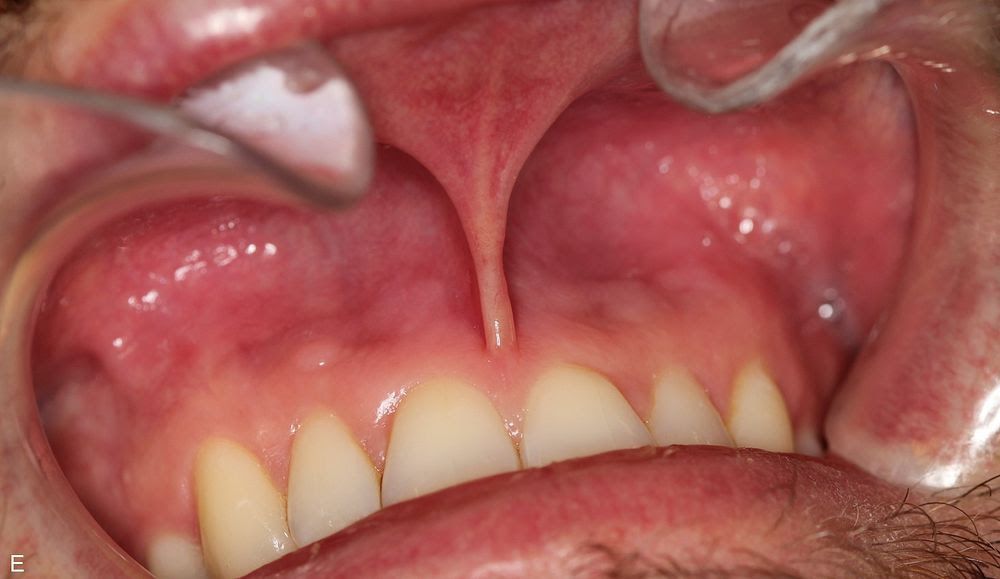

Before the trial, 43.5% of the dentists reported having irritated gums, and 95.7% had visible oral mucosal snus lesions, which are pathological changes characterized by discoloured, thickened and wrinkled mucosa due to snus use. The results showed significant improvements: the incidence of irritated gums dropped from 43.5% to 4.3%, while the presence of oral mucosal snus lesions decreased from 95.7% to 65.2%. The severity grade of these lesions was also reduced by 51.9%. After the trial, 74% of participants felt their gums were significantly healthier.